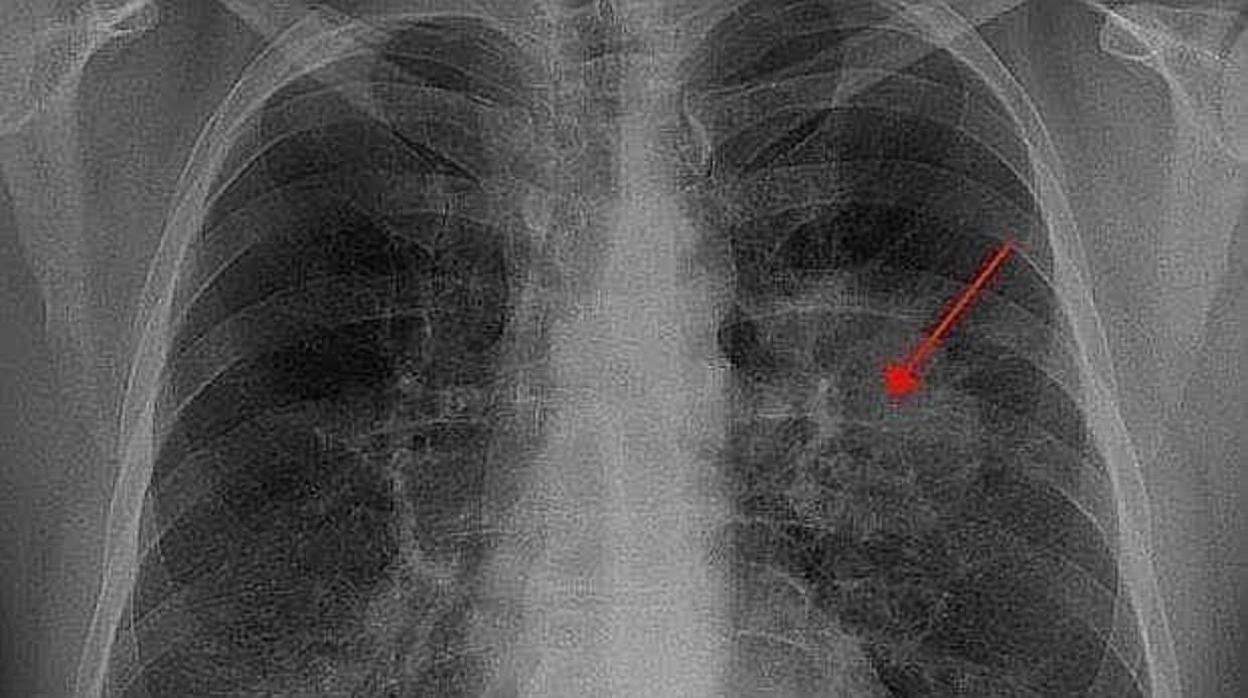

Radiografía de un paciente con cáncer de pulmón Archivo